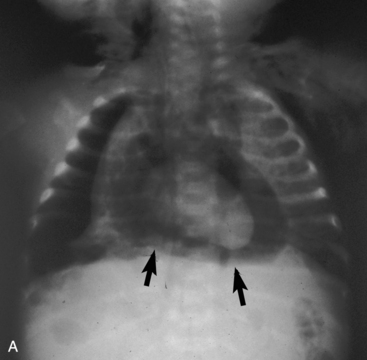

Check the continuity of vertebrae, ribs, scapulas, and clavicles for fractures and bony destruction. The ribs and intercostal spaces should be symmetrical. A fracture often will create a dark line in the bone because of separation of the bone fragments (Fig. 10-3). The vertebral bodies, particularly the cervical vertebrae, should be checked closely for fractures if the child has been admitted following trauma. The presence of multiple rib fractures, especially both posterior and anterior, and in various stages of healing is pathognomonic (positive predictive value of 95% or higher in children 3   years of age and younger) for child abuse.4 Healing fractures often have an enlarged area consisting of cartilage and woven bone creating a callus. Rib notching, or erosion of the underside of ribs caused by enlargement of the intercostal arteries, can be seen in older children with coarctation of the aorta, because the intercostal arteries become enlarged to carry collateral circulation around the area of coarctation into the descending aorta. Abnormalities of the ribs may be noted if the child has had surgery to alter the size or shape of the rib cage. Splinting can produce narrowing of the intercostal spaces on one side of the chest.

image

Fig. 10-3 Rib fractures. This chest radiograph of an 18-month-old girl was obtained as part of a series of films to evaluate for evidence of injuries caused by inflicted trauma. The child was admitted to the pediatric critical care unit with altered mental status, subdural hemorrhages, bilateral retinal hemorrhages, and areas of ecchymosis in various stages of healing. There are multiple healing rib fractures of different ages bilaterally, both medially and laterally (some indicated by the arrows) with no previous physician visits for trauma and no explanation for the injuries. Note the position of the tip of the nasogastric tube in the distal esophagus.